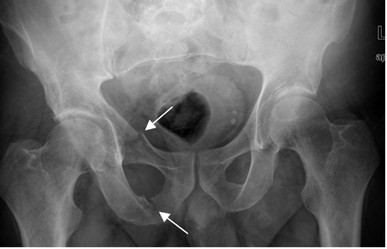

Fig 40. Trauma de pelvis. Compresión AP.

A: Rx AP. Fracturas oblicuas de los ramos ilio e isquiopúbico.